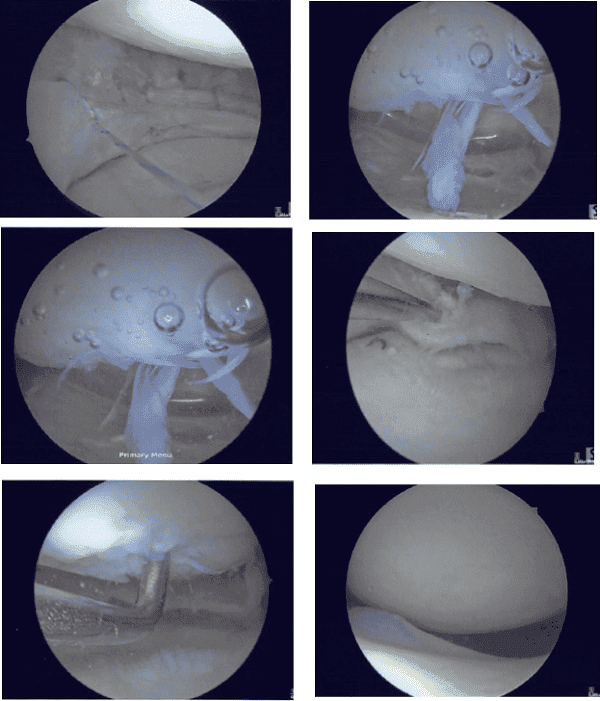

El portal de entrada medial se realizó utilizando una aguja espinal. El examen de la rodilla mostró artritis de troclea grado 3 a 4 de artritis de la troclea, artritis de grado 2 a 3 de la faceta tardía de la rótula, artritis de grado 2 a artritis de grado 3 del cóndilo femoral medial, reparación previa del menisco medial debido a las suturas, así como desgarro largo de la unión meniscocapsular del menisco medial de la rodilla izquierda.

Hubo cierto desgarro y deshilachamiento del menisco lateral en el margen medial, que se resolvió con la afeitadora y la meniscectomía para estabilizar. márgenes. El LCA (historia de la reconstrucción del LCA) mostraba deshilachados en la muesca intertroclear, pero el LCA estaba intacto.

Se realizó el desbridamiento del LCA. Se realizó una limpieza de la unión meniscocapsular del menisco medial. Se realizó raspado tanto del menisco como de la cápsula en preparación para la reparación utilizando afeitadora y raspas artroscópicas.

Se realizó condroplastia del cóndilo femoral medial, troclea y faceta lateral rotuliana. Se tomó la decisión de reparación. Toda la reparación interna del menisco medial se realizó utilizando fijadores FasT, cinco curvados y dos curvados invertidos de forma secuencial.

Tras la reparación, se comprobó que el menisco estaba estable. Se tomaron las fotos finales. La rodilla estaba completamente irrigada. Le quitaron el endoscopio y drenaron la rodilla. El cierre se realizó con nylon #4-0. El vendaje se hizo usando 4×4, ABD, Webril y Ace wrap.